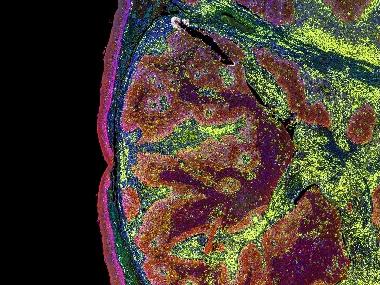

In uno studio condotto presso il Georgia Cancer Center, topi geneticamente modificati per rispondere agli antigeni umani sono stati esposti ad un antigene comunemente riscontrato nel cancro del fegato umano. L’antigene ha attivato il sistema immunitario e alcune cellule T di topo hanno sviluppato la capacità di attaccare il cancro del fegato. I ricercatori hanno prelevato geni che codificano i più potenti recettori dell’antigene del cancro del fegato presenti sulle cellule T del topo e li hanno trasfettati in cellule T umane. Le cellule T umane ingegnerizzate risultanti hanno anche preso di mira il cancro, senza danneggiare cellule epatiche sane. Uno degli autori dello studio Yukai ha dichiarato: “Queste cellule T sono molto potenti e possono uccidere il cancro del fegato umano sia in un piatto che in un topo”. Come riportato nella rivista Hepatology , i grandi tumori del fegato in topi relativamente piccoli hanno iniziato a regredire circa 20 giorni dopo il trattamento e sono scomparsi completamente entro il 41° giorno con l’aiuto di uno dei recettori. Secondo i Centers for Disease Control and Prevention, evidenzia Giovanni D’Agata, presidente dello “Sportello dei Diritti”, l’incidenza di nuovi casi di cancro al fegato nel Regno Unito è aumentata del 38% tra il 2003 e il 2012. Nel 2012, quasi 23.000 persone sono morte per cancro al fegato, che rappresenta un aumento del 56% dei decessi dal 2003. Successivamente, Yukai prevede di collaborare con l’ospedale Piedmont Atlanta (USA) per recuperare cellule T, cellule cancerose del fegato e tessuto sano da pazienti sottoposti a intervento chirurgico e per posizionare i geni del recettore del topo su quelle cellule T. Le cellule saranno quindi monitorate in un piatto per vedere quanto combattono i tumori del fegato e come reagiscono ai tessuti sani. Yukai afferma che se le cellule T producono un attacco robusto contro il cancro, senza danneggiare le cellule sane, il prossimo passo sarebbe testare il trattamento negli studi clinici. Ora che abbiamo questi geni del recettore delle cellule T, potremmo essere in grado di umanizzare i geni per aiutare i pazienti, ha dichiarato il co autore Yukai He.